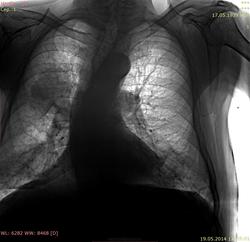

Пациент 1939 г.р., обследуется с подозрением на нео ротовой полости, диагноз не верифицирован. Легочный анамнез - без особенностей. Исследование ОГК не проводилось несколько лет, архива нет. Жалоб нет, температура нормальная. Сколиоз.

Наверное, это не очень похоже на мтс? Скорее cr легкого или м.б. tbc?

Периферический с централизацией, уж близко к корню прилежит, хотя по боковому больше похоже на центральный ВДБ с  неполным ателектазом S1.

Мне кажется больше на мтс похоже, структура какая-то размытая для образования и гиповентиляции не вижу. Скажите потом результат, если будет дообследвание.

Это справа, а слева корень имеет мт из из правого? ИМХО - если не МТ , то лимфомаdevil, или другая ома , но не рак...